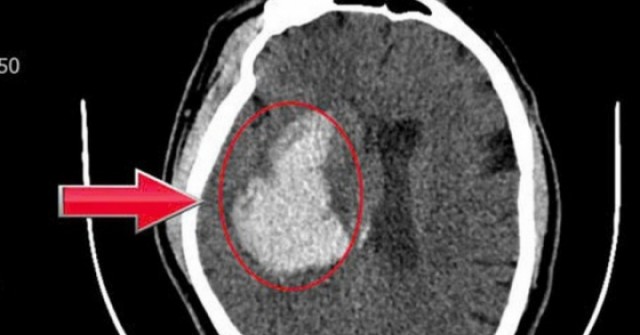

Hình ảnh chụp cộng hưởng từ đường mật cho thấy hệ thống đường mật giãn rộng, nguyên nhân do sỏi nằm ở đoạn thấp ống mật chủ.